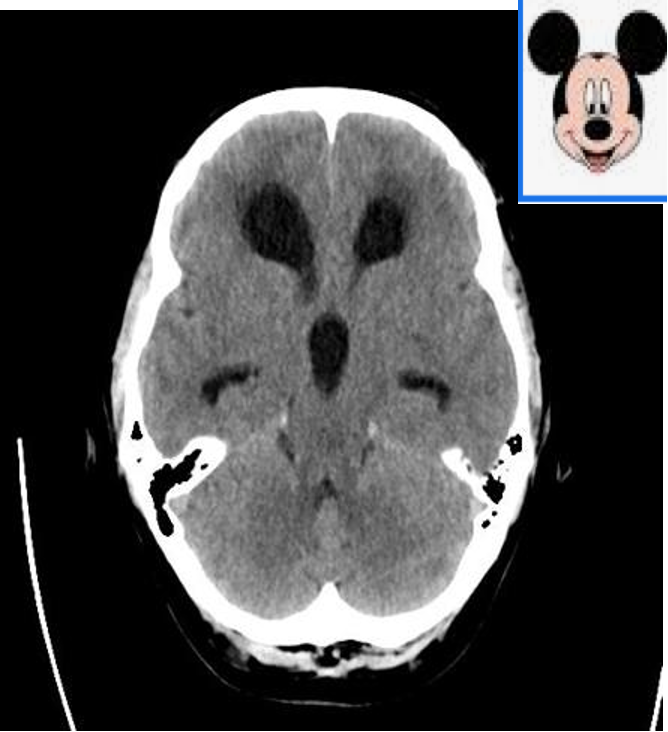

- Mickey Mouse ventriclesĀ (enlargedĀ lateralĀ andĀ third ventricle)

Hydrocephalus:

Third and both lateral ventricles are dilated but the fourth ventricle is normal. It shows that the Obstruction is above the level of fourth ventricle. In this case blockage is in the aqueduct.